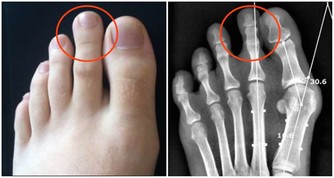

患者在發病前會有臉部、舌頭、唇部麻木等表現,最明顯的還會出現嘴歪流口水等。有時患者一側的肢體會出現麻木,肢體不靈活,使不上勁。